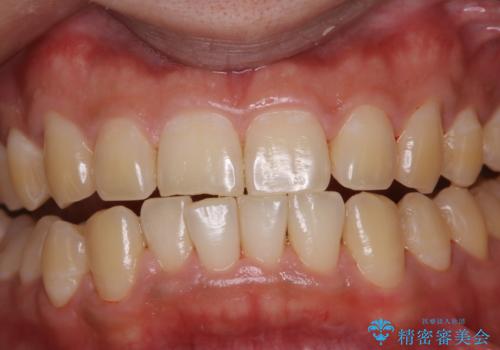

数年ぶりに歯のクリーニング(PMTC)